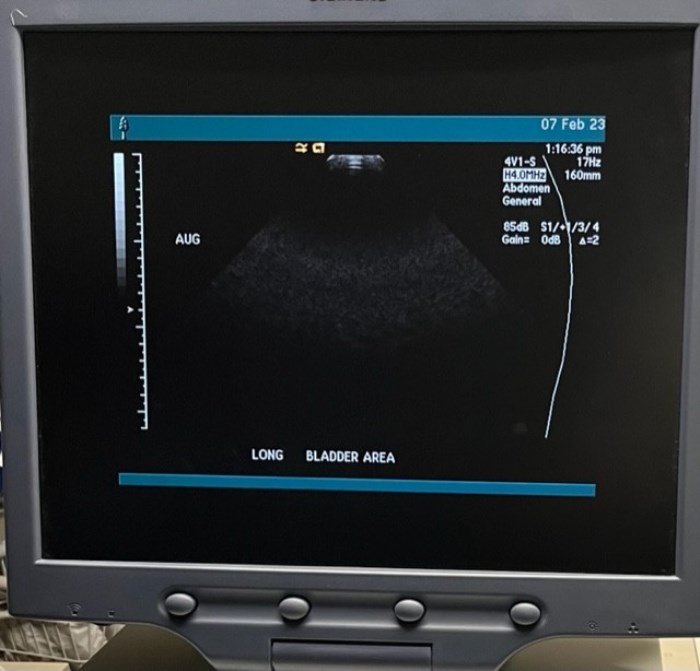

Siemens Sequioa Ultrasound

Pre-owned. In good working condition. Shown as is. Siemens Sequoia Ultrasound. DOM: 2006

Probes: 15L8w, 4V1, 10V4, 6L3, 4C1